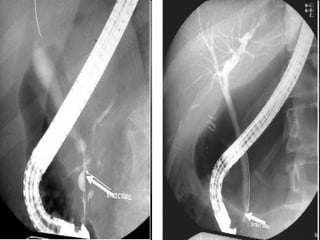

• Endoscopic retrograde

cholangiopancreatography (ERCP)

was performed in cholestatic patients

younger than 6 months suspected of

having an extrahepatic cause of

cholestasis, particularly biliary

atresia. In this series, the sensitivity of

ERCP for diagnosing biliary atresia

was 92% and specificity was 73%..

Biliary atresia, type B: cholangiographic features.

Intraoperative cholangiography is performed by catheterization

of the gallbladder (asterisk) and injection of contrast. This

infant has an extremely hypoplastic but patent common bile

duct (arrow). There is no filling of the common hepatic duct or

intrahepatic ducts. This is consistent with Type B biliary atresia.

ERCPERCP • Endoscopic retrograde cholangiopancreatography(ERCP) was performed in cholestatic patients younger than 6 months suspected of having an extrahepatic cause of cholestasis, particularly biliary atresia. In this series, the sensitivity of ERCP for diagnosing biliary atresia was 92% and specificity was 73%..

Biliary atresia, typeB: cholangiographic features. Intraoperative cholangiography is performed by catheterization of the gallbladder (asterisk) and injection of contrast. This infant has an extremely hypoplastic but patent common bile duct (arrow). There is no filling of the common hepatic duct or intrahepatic ducts. This is consistent with Type B biliary atresia.

Importance of ERCP •ERCP is not an alternative to noninvasive imaging but can avoid unnecessary surgical procedures in approximately 25% of cases. They therefore recommended that ERCP be performed before explorative laparotomy in all patients suspected of having biliary atresia.